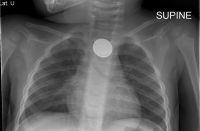

The key to differentiating a button battery from a coin is to magnify or zoom into the image looking for a double ring or halo. This x-ray shows a small ridge on the object that this toddler has swallowed – a button battery.